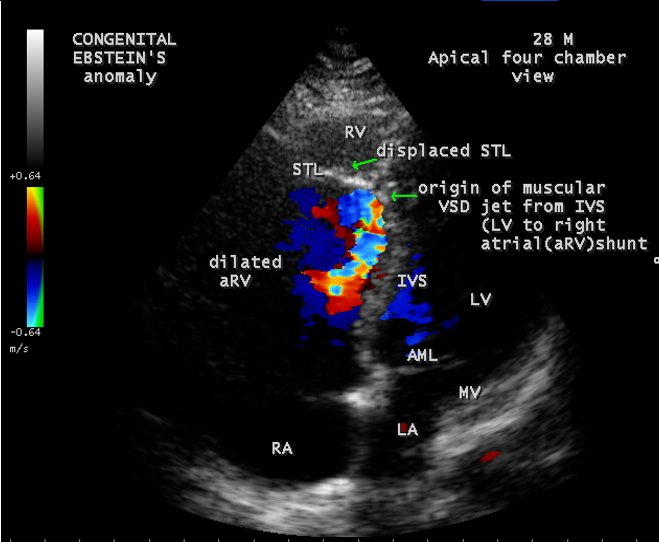

A 28-year old male presented with cyanosis and auscultation revealed a ‘sail sound’ ( loud tricuspid component of first heart sound due to increased tension developed by the large anterior leaflet as it reaches the limits of its systolic excursion- an important sign of anterior leaflet mobility), a ‘cadence’ quality of quadruple rhythm due to wide splitting of first and second sounds ( due to complete right bundle branch block), atrial and ventricular filling sounds (summation of these sounds due to prolonged PR interval). ECG revealed the features of Ebstein’s anomaly as shown in Figures 11 and 12. X-ray chest revealed the Ebstein’s configuration as shown in Figure 13. 2D echocardiography revealed a ‘sail-like’anterior tricuspid leaflet forming a ‘muscular curtain’ in between the inflow and trabecular parts of the right ventricle as an ‘imperforate membrane’ with a ‘pinhole’communication, associated with a muscular VSD (ventricular septal defect) in the proximal, atrialized compartment of right ventricle suggesting an ‘atretic” (‘imperforate’) Ebstein’s anomaly as shown in Figures 14 to 27.

The anterior tricuspid leaflet is not involved in the process of downward displacement, it may be abnormally inserted occasionally and Shiina, et al documented the apical displacement of anterior tricuspid leaflet in 14% of cases echocardiographically [39]. The anterior leaflet forms a large, sail-like intracavitary curtain as in Figures 14, 25 and contains muscular strands instead of consisting entirely of a fibrous membrane as in the normal tricuspid valve [40]. It is potentially mobile with a brisk sail-like movement as shown in Figure 21 to 24 [41], free bloating with a ‘whipping motion’ across the right ventricular outflow tract (RVOT) as shown in Figure 26 and in some cases, the movement is restricted due to its adherence to the ventricular wall as in Figure 1 and 2, 4 and 9. It is often fenestrated, may in part be musculaized , inserting into the trabeculations of the right ventricle (RV) as in Figure 28 and rarely, the anterior leaflet forms an ‘atretic’ membrane that spans the midportion of the right ventricular cavity as in Figure 16.

An interatrial communication is present in 80 to 94% of patients with Ebstein’s anomaly [50]. Ebstein believed that “regurgitation of blood into the right atrium caused its dilatation and prevented complete closure of the valve of foramen ovale”. The majority of hearts with Ebstein’s anomaly have a patent foramen ovale (67%) and in more than one third of cases, the interatrial communication is an ostium secundum defect as shown in Figures 1 and 2 . An intact atrial septum is rare and usually seen in adults as in Figure 4. The ventricular septal defect may be localized in either the proximal as shown in Figure 19 or the distal right ventricular compartment and it can be muscular with an incidence of 4% in clinical series and 12% in autopsy studies. The hearts in which the opening is proximal to the displaced tricuspid valve, a left ventricular to right atrial shunt may occur as shown in Figure 20

Ebstein’s original case was an example of obstruction at the tricuspid orifice by a membrane dividing the right ventricle into two halves as shown in Figure 16 of a 28-year old cyanotic male with ECG and X-ray characteristics as in Figure 11 to 13. suggesting an advanced spectrum of Ebstein’s malformation , necessitating RV exclusion techniques such as Starnes’ procedure. The florid case of Ebstein’s anomaly with the insertion of leaflet tissue along with ventricular walls as a ‘blanket’ as in Figures 28 and 29 in a 30-year old cyanotic male may go for an initial palliation with bidirectional Glenn shunt (cavopulmonary anastomosis). The other variants of moderate degree of leaflet tethering with varying degrees of regurgitation, but an intact basal leaflet attachments with atrioventricular junction as in Cases 1 and 2 may need a definite repair. In Ebstein’s mitral valve as in Figure 32 in a 10-year old boy, the downward displacement of functional annulus > 0.8 cm/m2 is not particularly striking and tends to affect the septal leaflet (anterior mitral leaflet) alone. The valve is thickened and mildly regurgitant due to rheumatic involvement rather than an anatomic cause.